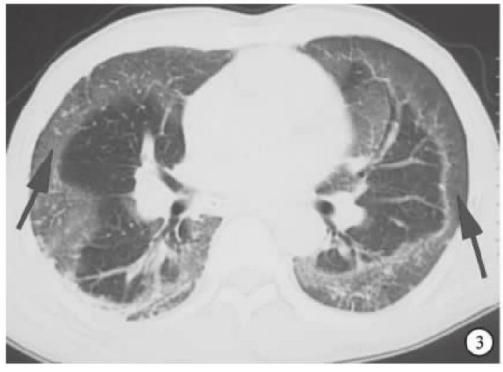

流感,特别是甲流,也会表现为胸膜下为主的磨玻璃,但是出现的几率小于新冠肺炎。

下面的患者,就是甲流病毒性肺炎。